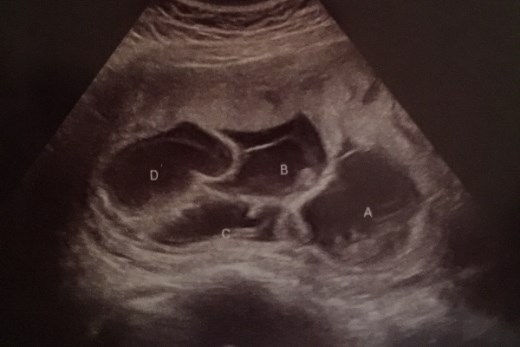

Когато дошло времето на първия ултразвук, настъпила истинска изненада. Двамата дори и не предполагали какво ги очаква, когато лекарят им показал нещо наистина рядко. Кайли била бременна не с едно, не дори с две, а с цели четири бебета.